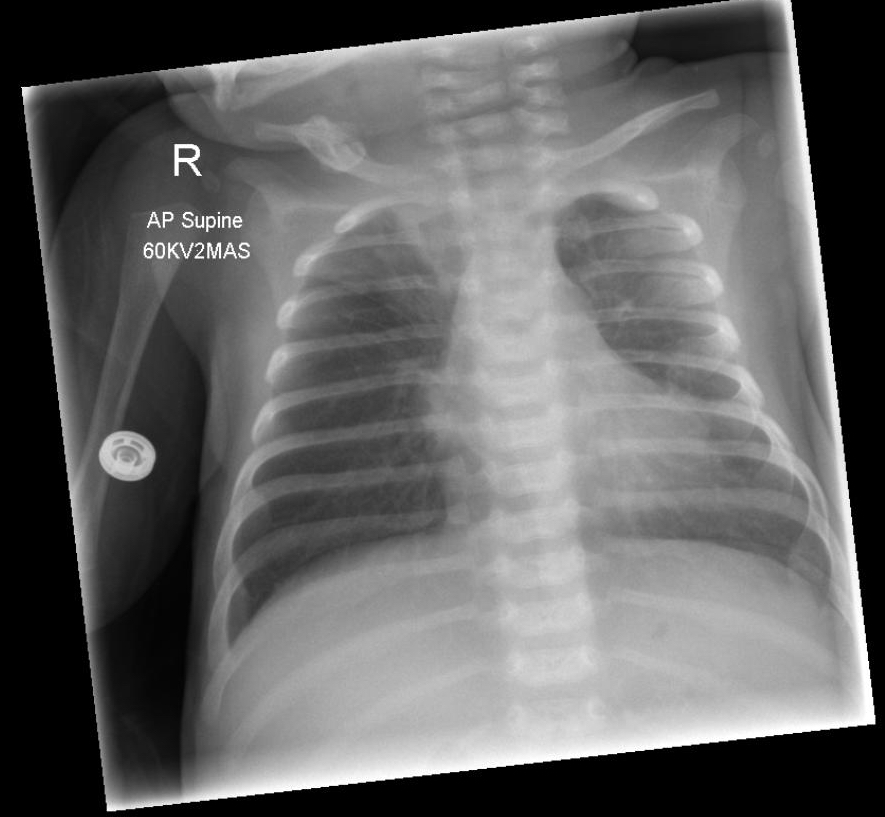

Book rapid access paediatric clinic in the morning at the hospitalYou contact the outpatients department and arrange the appointment, also instructing the mother to bring him back if he deteriorates further. She thanks you for you time and care. ------------- You are now the attending paediatric trainee in the Emergency Department (ED). An ambulance arrives with a 4 month old infant who is having a seizure. The ambulance crew have put him in the ‘recovery’ position, put an oxygen mask on him, attached monitoring and administer diazepam per rectum. His mother is very frightened, saying that he had been a little unwell with a cold, that the doctor said he was okay that he has had all his immunisations, that he was going to come back in the morning to see the paediatricians. She was taking home after seeing the doctor when he started staring, then his eyes rolled up and he started shaking all over. She cried out and a passer-by called an ambulance, and that he is still shaking. He is taken into the resus area and monitoring attached. His capiliary blood glucose is 5.6 mmol/L. A cannula is sited and he is examined: HR 170/min, RR30/min, SaO2 95% in mask oxygen, BP 95/45 mmHg Airway clear Chest moving well, large airway inspiratory crackles Heart sounds normal, capiliary refill 3-4 seconds Abdomen soft Moving all limbs rhythmically 3 beats/sec. Anterior fontanelle full Unresponsive. He is given intravenous lorazepam and shortly after the seizure terminates. He remains stable from a cardiorespiratory point of view. The resuscitation team smile and leave you to continue the management. Some blood tests that were sent on admission now have results available. Hb 103 g/L Wcc 16.3 x 109/L Plats 341 x 109/L Urea 3.8 mmol/L Na 141 mmol/L K 4.6 mmol/L Creat 42 micromol/L Urine is sent for microscopy and culture. A mobile chest radiograph is also arranged. It is twenty minutes now since his seizure terminated. You review him and take a history from his mother, who is now less distressed. He was born at term normally. He is her first baby – it was a surprise for her and her boyfriend but she was very pleased that she was having a baby. He has been well up to this episode, and has had all the required immunisations. He is beginning to use his hands now, smiles, and follows moving objects with his eyes. He was well up until the last 3 days, when he developed a runny nose and then a cough. She does not think her son has had a temperature. Since then he has been increasingly irritable and she cant seem to settle him. Feeding is not consistent and regular like it was before. She has also noted a new mark on his skin and wonders if it is ringworm. She looked it up on the internet. He has two other birthmarks. He is still very sleepy and barely responsive to pain. His respiratory rate is 30/min, temperature 37.4C and HR 120/min, but otherwise his examination is unchanged. The new marks: The birth marks: What would you like to do now? |